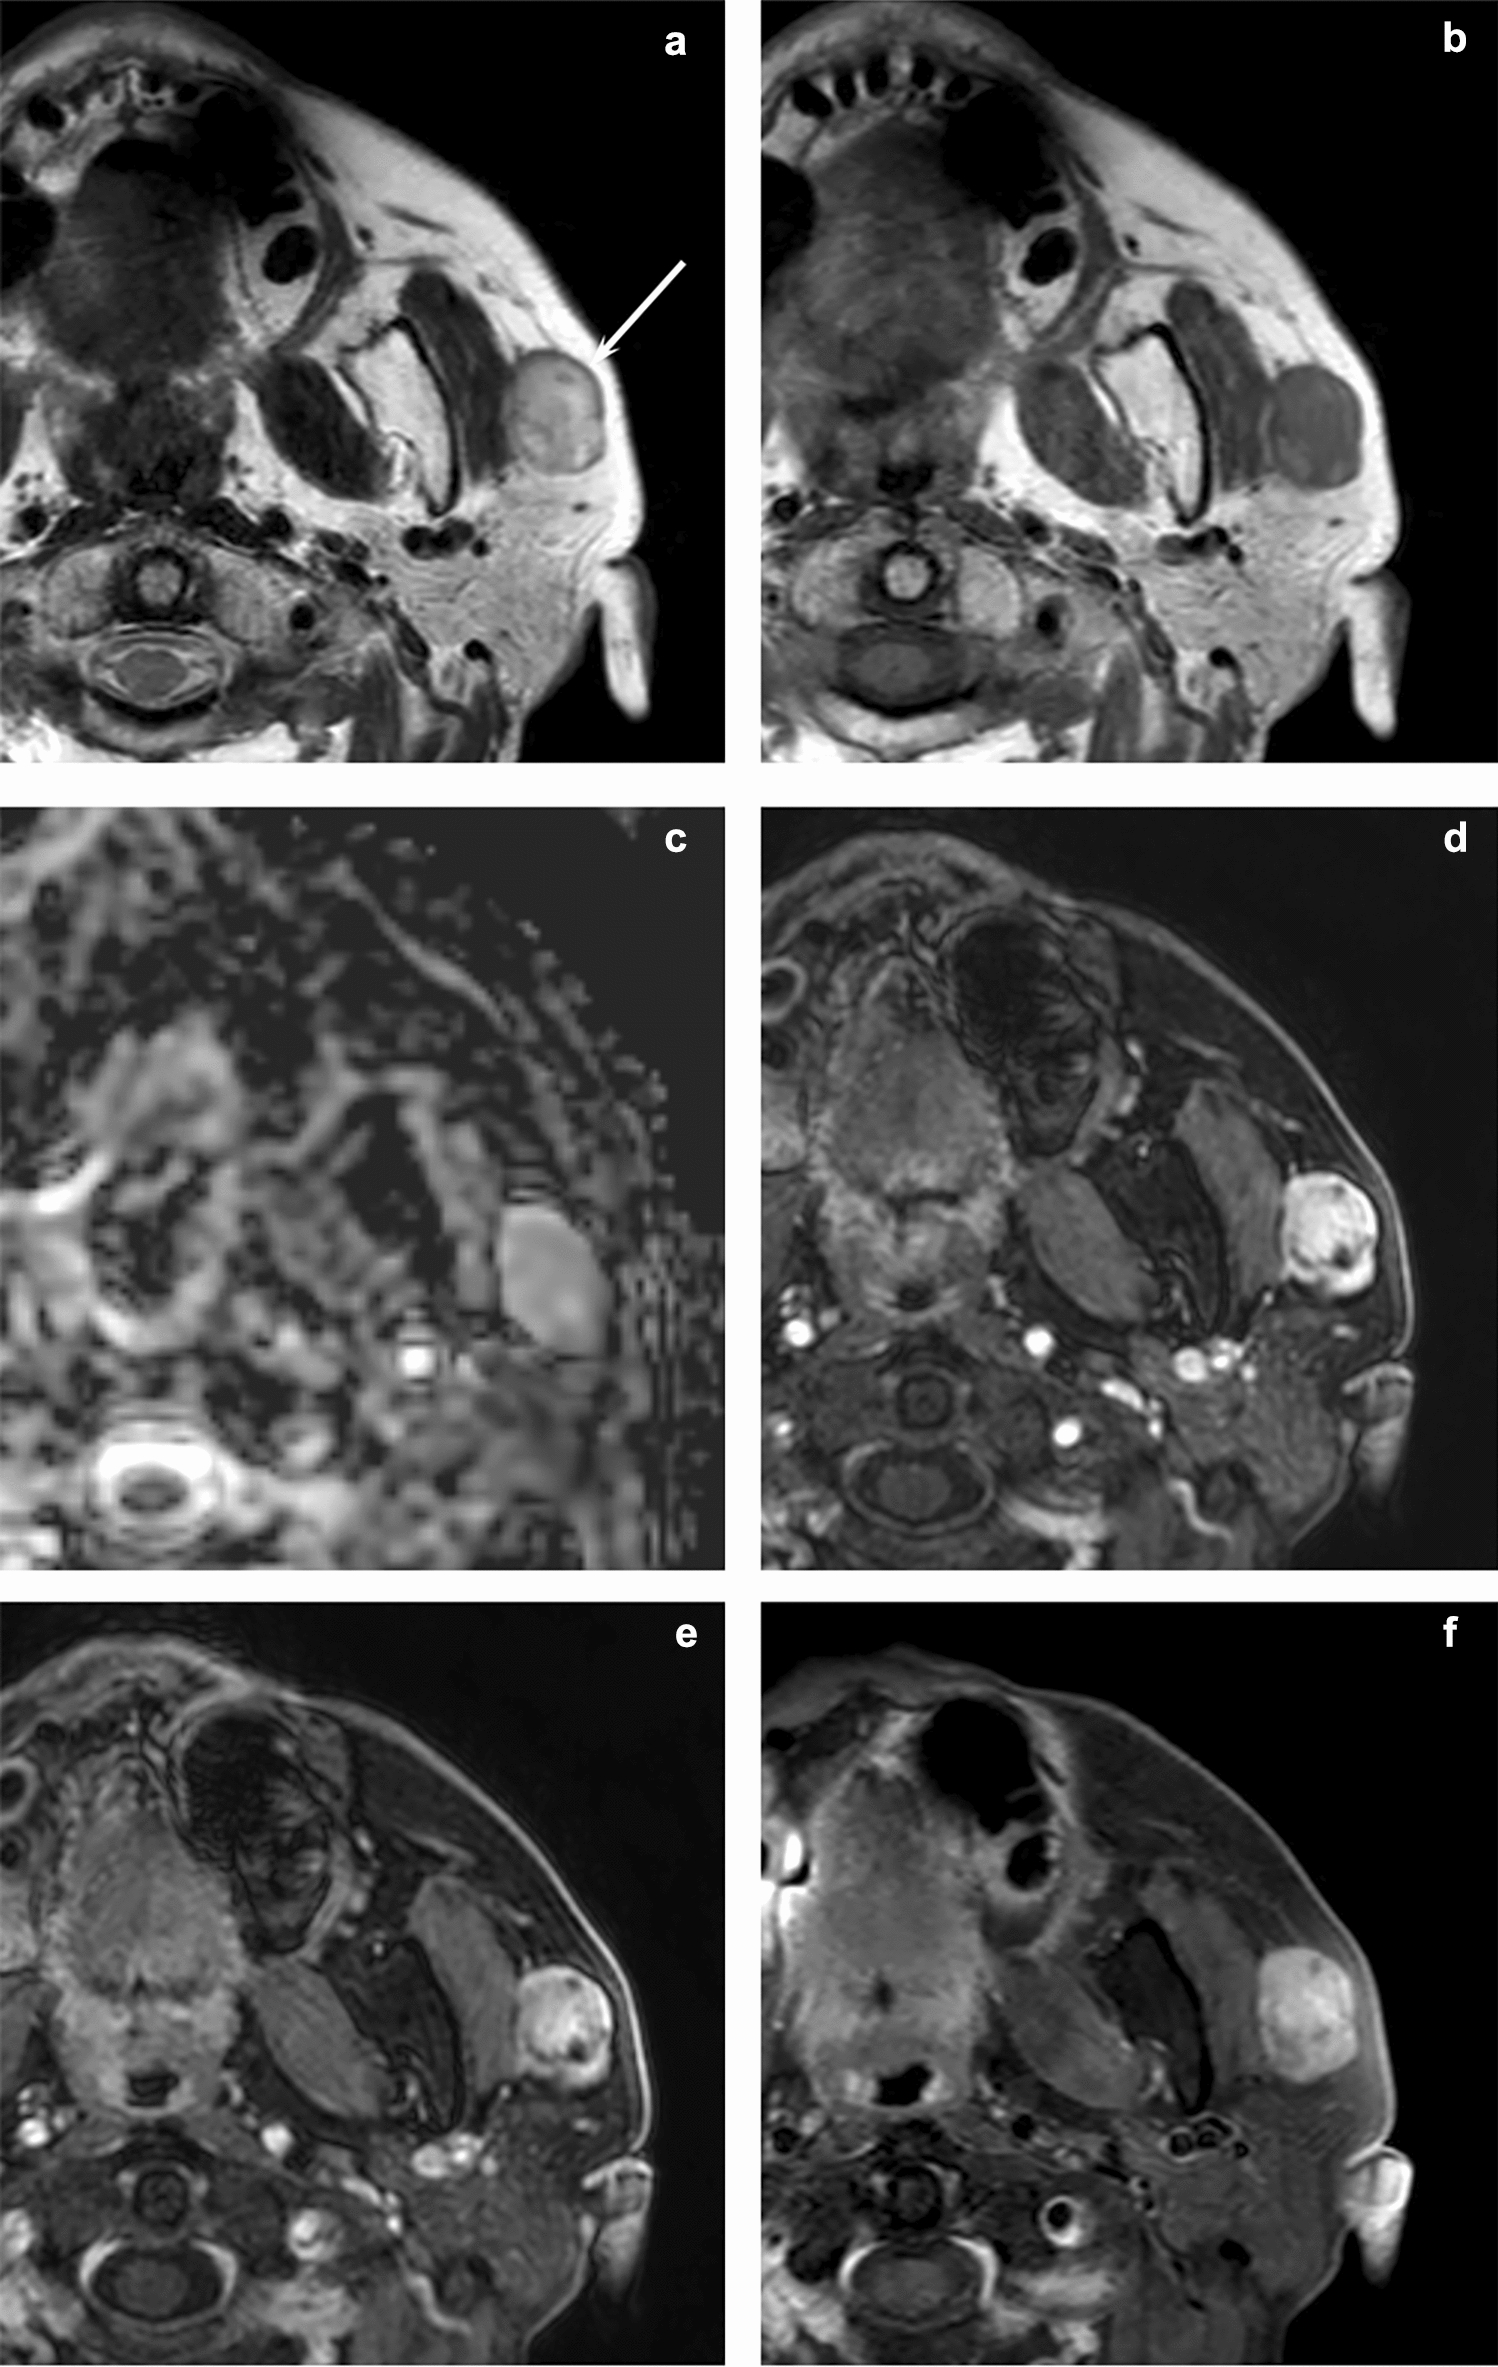

MRI and CT features of head and neck myoepithelioma: comparison with parotid pleomorphic adenoma

To evaluate the MRI and CT features of head and neck myoepithelioma in comparison with parotid pleomorphic adenoma. This r...